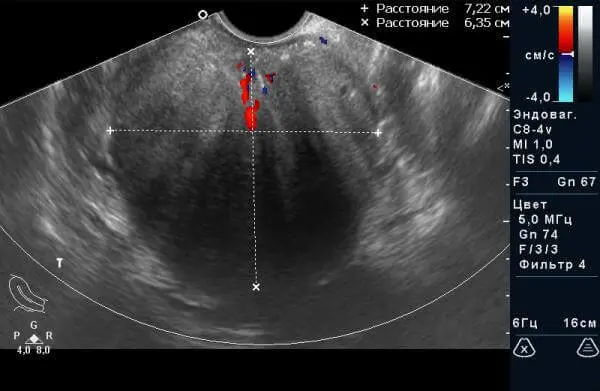

Рис.2. Доброякісна гіперплазія передміхурової залози (до лікування).